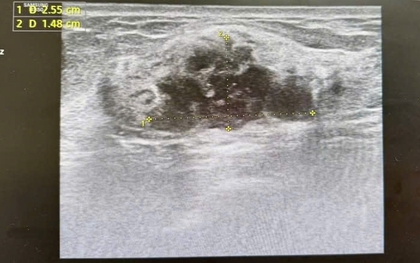

Người phụ nữ 60 tuổi ở Hà Nội phát hiện ung thư vú giai đoạn sớm trong lần khám sức khỏe định kỳ dù cơ thể hoàn toàn bình thường, không đau hay sờ thấy khối u.